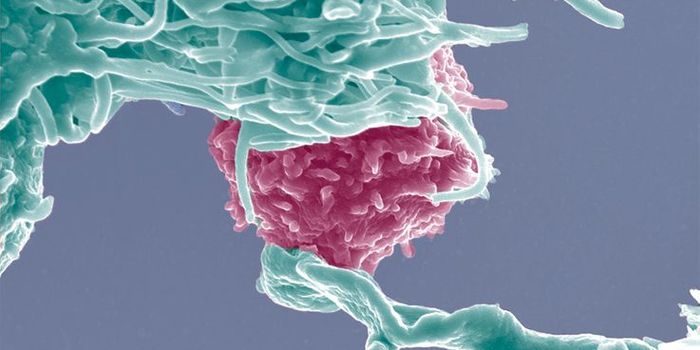

DEC 19, 2015ImmunologyDendritic cells use phagocytosis to break up molecules from pathogens to present on their cell surface to warn other lym ...